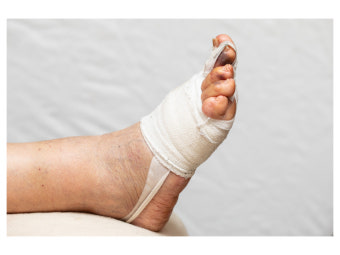

3. 회복 기간과 주의사항

수술 후 회복에는 일반적으로 4주~8주가량이 소요되며, 수술 방법과 환자의 회복력에 따라 달라질 수 있습니다.

- 초기에는 보조 신발이나 목발을 사용하여 체중을 발에 싣지 않도록 해야 합니다.

- 수술 부위에 붓기와 통증이 남을 수 있으며, 냉찜질과 약물로 조절합니다.

- 병원에서 알려주는 재활운동을 꾸준히 해야 기능 회복 속도가 빨라집니다.

- 수술 후에도 잘못된 신발 습관이나 생활습관이 반복되면 재발할 수 있습니다.